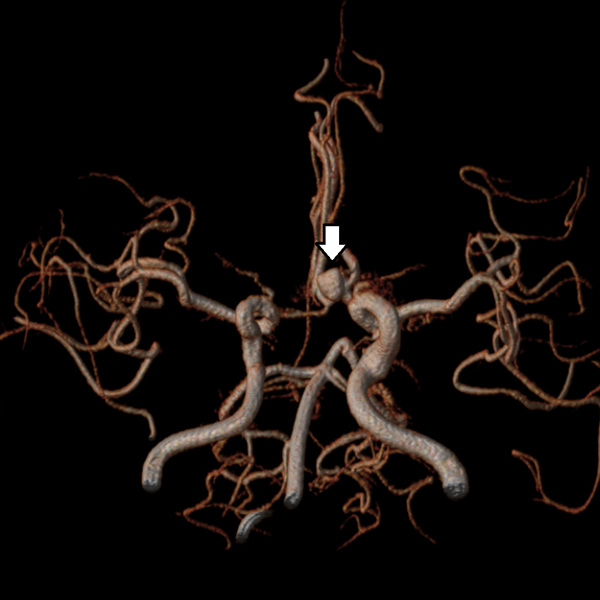

MRA検査

MRIの撮影技術を使って、血管を描出する方法です。頭蓋内外の重要な動脈(総頸動脈、内頸動脈、ウィリス輪、椎骨動脈、脳底動脈)の変化をとらえることができます。

MRIではCT検査と同様、腫瘍の大きさや形、数などがわかります。また、MRAでは脳動脈瘤、脳梗塞、脳動静脈奇形、もやもや病、閉塞性動脈病変などの脳血管障害がわかります。脳ドックでは、くも膜下出血の原因となる脳動脈瘤のスクリーニング検査としてよく用いられています。